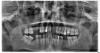

Палыч Опубликовано 15 марта, 2010 Поделиться Опубликовано 15 марта, 2010 Люди, ну черкните хоть что нибудь дельное!1. ревизия каналов 14, 12, 25, 26 с последующим ВКВ и коронки.2. лечение 27, 283. Ортодонтия.4.Имплантация в позиции 15, 16, 21, 36, 46. Ссылка на комментарий

Cave Опубликовано 15 марта, 2010 Автор Поделиться Опубликовано 15 марта, 2010 1. ревизия каналов 14, 12, 25, 26 с последующим ВКВ и коронки.2. лечение 27, 283. Ортодонтия.4.Имплантация в позиции 15, 16, 21, 36, 46. Поговорил по варианту № 1, где 2х зубов вверху нет говорят что гайморовая пазуха близко и не готовы делать имплант. ЧЕМ ЗАКРЫТЬ ВРЕМЕННО ''амбразуру" ВПЕРЕДИ ЕСЛИ ИМПЛАНТАЦИЯ ? Ссылка на комментарий

Astronaft Опубликовано 15 марта, 2010 Поделиться Опубликовано 15 марта, 2010 (изменено) Вроде как ряд высокорискованных шагов имел место.Дважды неинтеграция: либо жесткая общая патология, либо аллергия, либо неразрешившееся местное воспаление, либо (вероятнее) нарушения протокола установки."Не могут синуслифт" - не причина его не делать. Изменено 15 марта, 2010 пользователем Astronaft Ссылка на комментарий